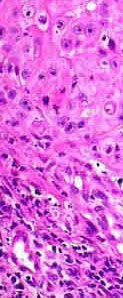

Epitehlial Tumours

Mesenchymal Tumours

Round Cell Tumors